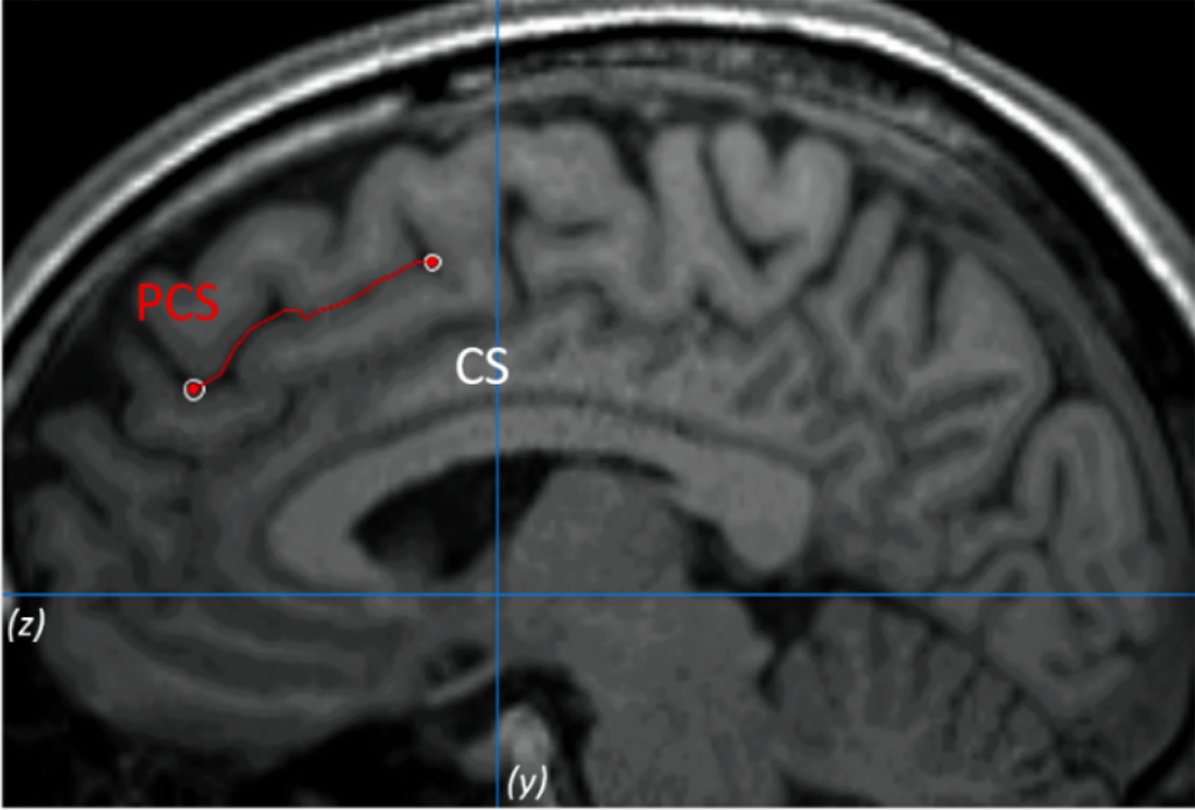

The PCS was measured following the measurement protocol described by Garrison et al. [Reference Garrison, Fernyhough, McCarthy-Jones, Haggard and Simons25] (see Figure 1 as an example). To validate the procedure, inter- and intrarater reliabilities were calculated. See the Supplementary Material for more details.

Figure 1. Example of the paracingulate sulcus (PCS) measurement on anatomical magnetic resonance imaging. The PCS is marked in red line and lies dorsal and parallel to the cingulate sulcus. Measurement was performed within the first quadrant (defined by z < 0 and y > 0) and on the fourth sagittal slice for both hemispheres.